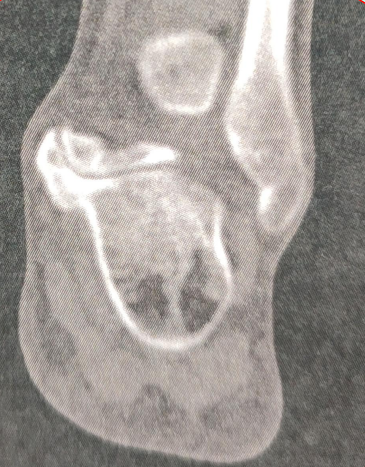

影像学表现

踝关节正位:距骨内侧结节至跟内载距突间有一长舍状骨块影,将跟骨与距骨连在一起,其间有一裂隙,形如关节,可以一侧明显。

踝关节侧位:跟骨距骨增大的两骨块呈唇状相吻,由后上斜向前下,内示裂隙。

特征影像:

C型征:是指跟距骨桥在侧位X线片,可见距骨头与载距突边缘轮廓组成环状高密度影。

CT是诊断跟距骨桥的金标准

• CT可发现关节周围退变范围和骨性桥接涉及关节面的范围。

• CT可鉴别骨性骨桥和非骨性骨桥。

• CT难以显示纤维性骨桥

展示一个跟距骨桥的病例